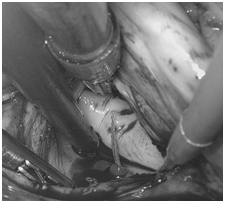

手术中,医生戴上3D眼镜,先在体外循环的设备支持下使阿福的心脏停跳,再在他的右侧胸部上打了3个“钥匙孔”,从肋骨间伸进镜头和手术器械。

阿福胸腔内的立体景象,即刻出现在医生眼前的显示屏上。医生看着显示屏,操控阿福体内的器械,为他切开心脏、取出鱼刺、挖掉心肌感染灶,并缝合切口。